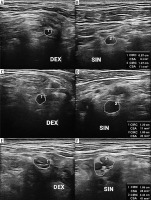

Figure 7

High-resolution ultrasound (HRUS) image of the suprascapular nerve (DEX – asymptomatic side, SIN – symptomatic side) with measurements in brachial neuritis due to neuroborreliosis. Side-by-side comparison. Images obtained by author with a 5-20 MHz linear probe of the Mindray Resona I9